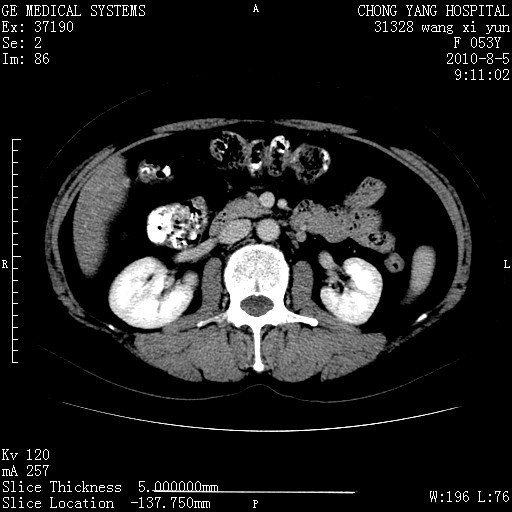

标题: CT28214:F41Y 血尿二十天,建议盆腔平扫加增强。

1)考虑肝左叶胆管细胞癌。2)脂肪肝。

支持胆管细胞ca。